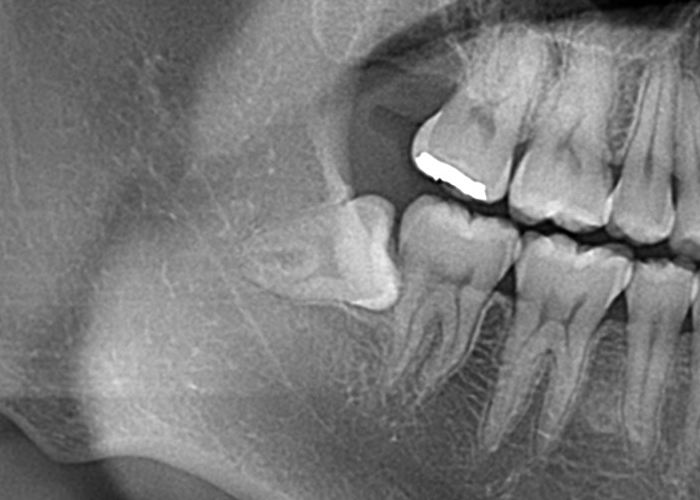

完全埋伏智歯(歯茎に完全に埋まっている)

完全埋伏とは、親知らずが完全に歯肉の下に完全に埋まっている状態を指します。

この場合、親知らずは通常、レントゲンやCTスキャンなどの画像検査でのみ確認できます。

完全埋伏の親知らずは、周囲の組織に直接的な問題を引き起こさない場合もありますが、将来的に問題を引き起こす可能性があります。

そのため、定期的な口腔検診や画像検査が重要です。